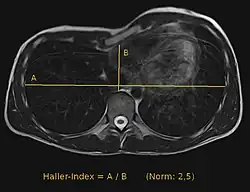

Haller-Index zur Quantifizierung einer Trichterbrust ermittelt mit der MRT. Der Normalwert beträgt 2,5. In diesem Beispiel liegt er bei ca. 4,7.

Anhand einer CT-Untersuchung oder einer Kernspintomografie lässt sich der Haller-Index ermitteln. Dieser Index wird weithin als Angabe für das Ausmaß der Trichterbrust verwendet. Er errechnet sich als der weiteste Abstand zwischen rechten und linken Rippen geteilt durch den kleinsten Abstand zwischen Brustbein und Wirbelsäule.[5] Ein anderes, mit einfacheren Mitteln zu bestimmendes Maß für die Tiefe der Trichterbrust ist der Abstand zwischen dem tiefsten Punkt der Trichterbrust und einem quer über die Brustwarzen gelegten Lineal.[6] Manchmal wird dieser Wert auch durch die Gesamttiefe des Brustkorbs dividiert.[7]